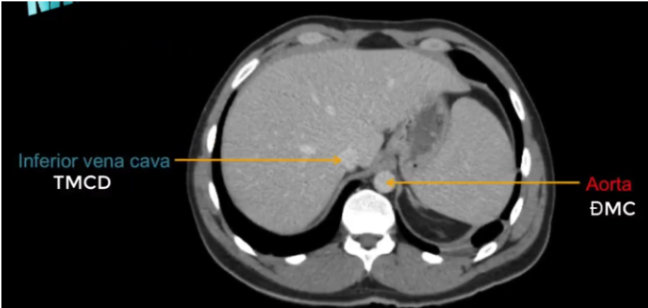

TM gan ở đâu? TM chủ dưới ? ĐM chủ?